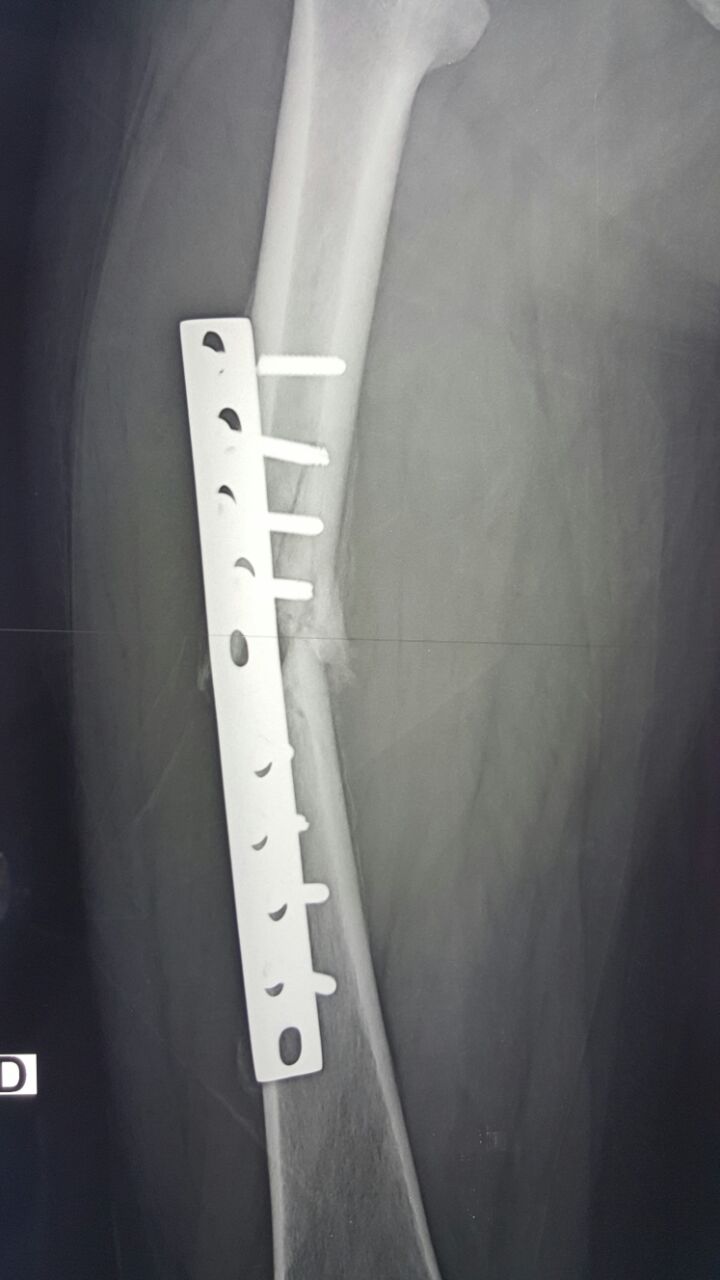

[Ortho] Несостоятельный остеосинтез

Снимки

Имя     : IMG-20160608-WA0001.jpg